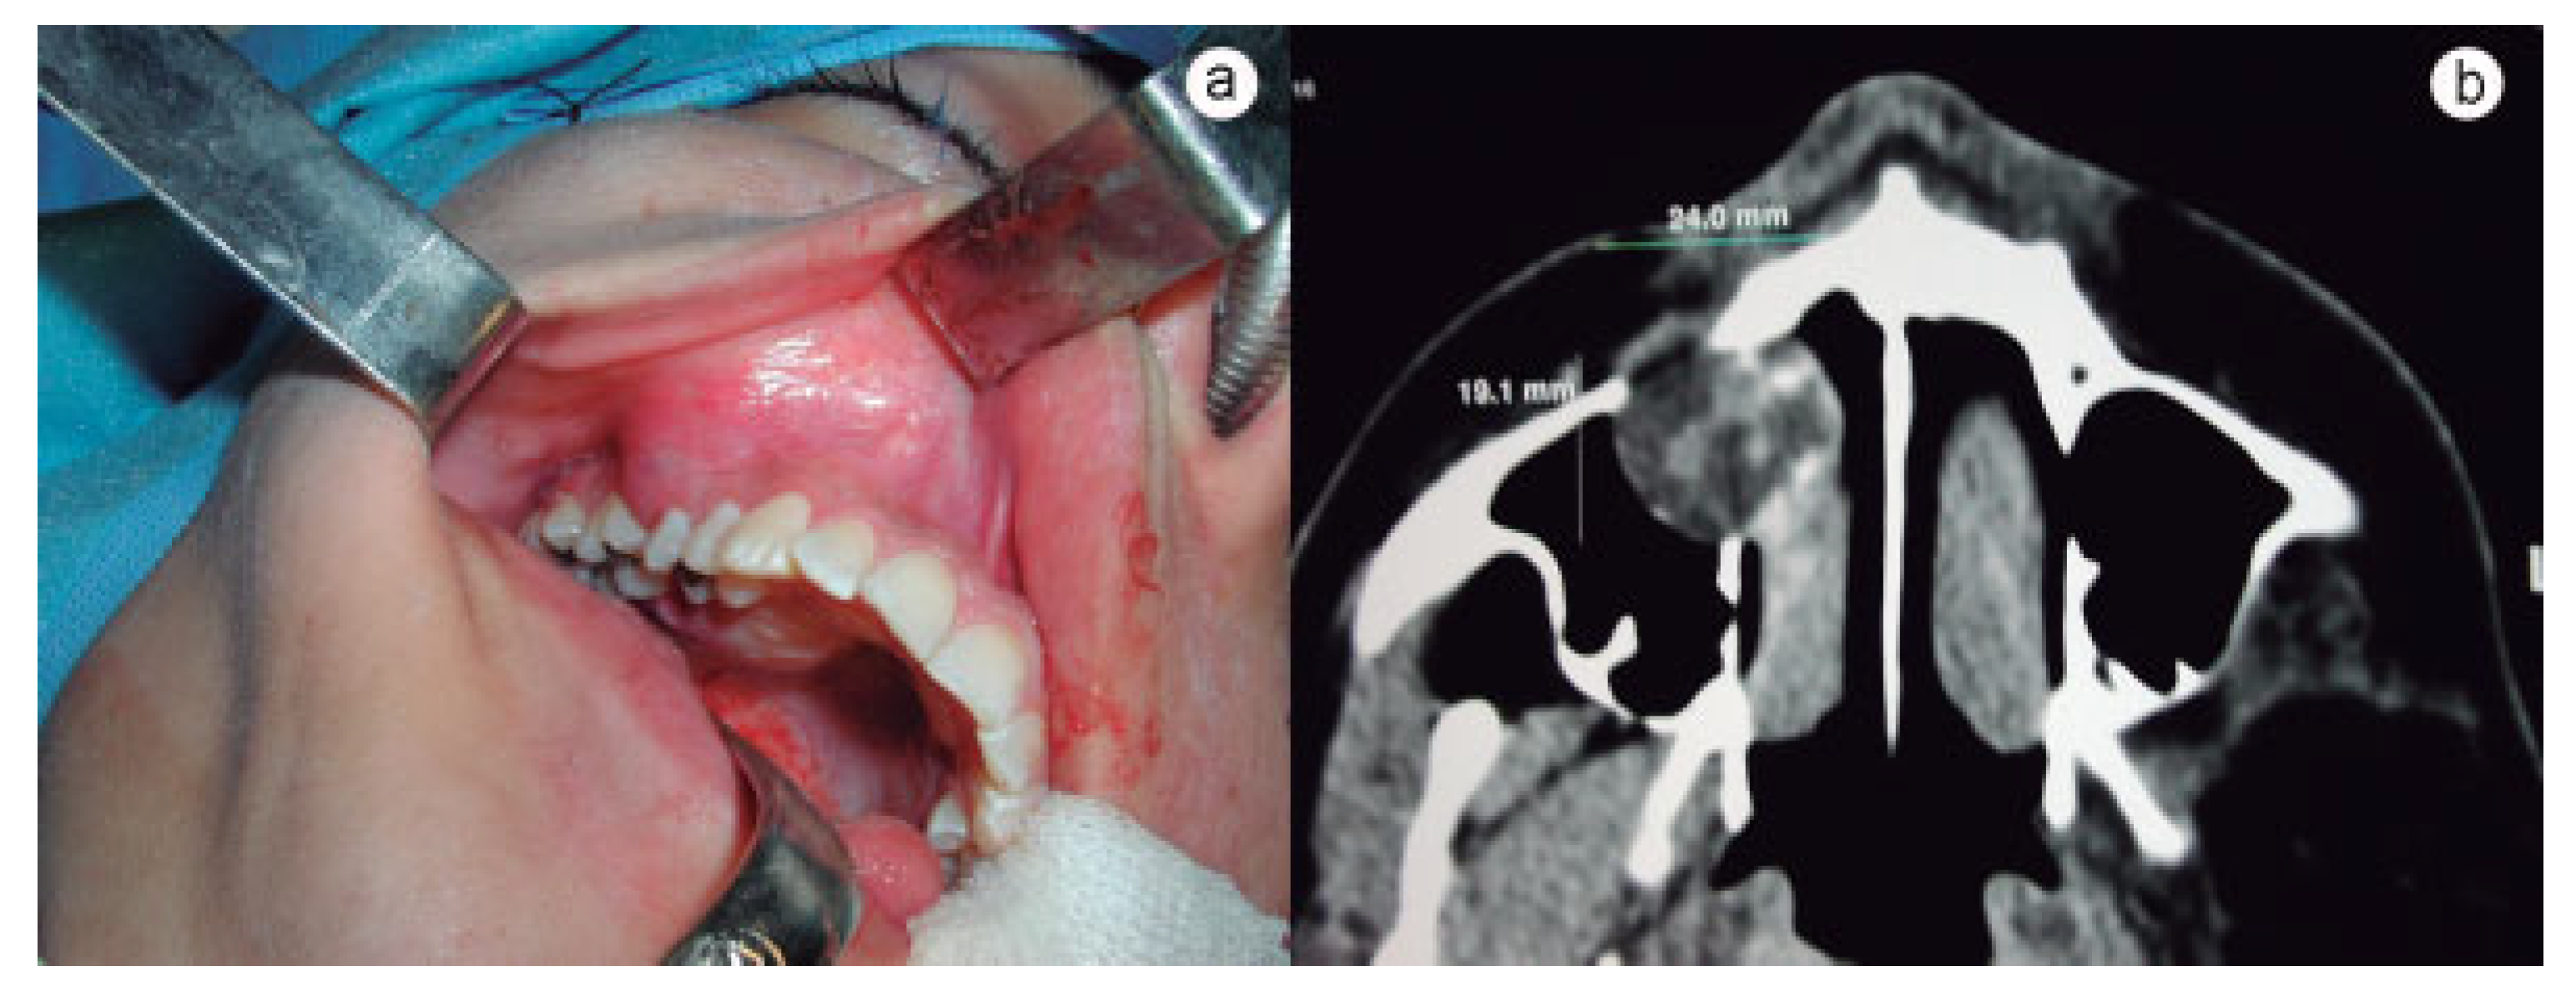

:Case History

Discussion